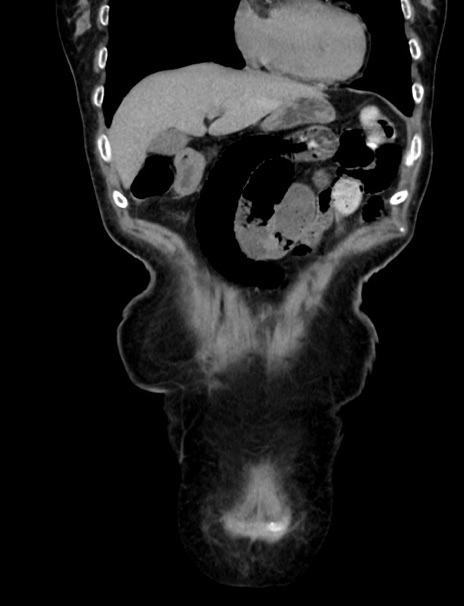

症例33(冠状断像)

【症例】70歳代 女性

【主訴】心窩部痛

【現病歴】延髄病変の精査・加療にて神経内科入院中。本日より心窩部痛あり。

【身体所見】右下腹部を中心に圧痛と反跳痛あり。

【データ】WBC 10900、CRP 0.02